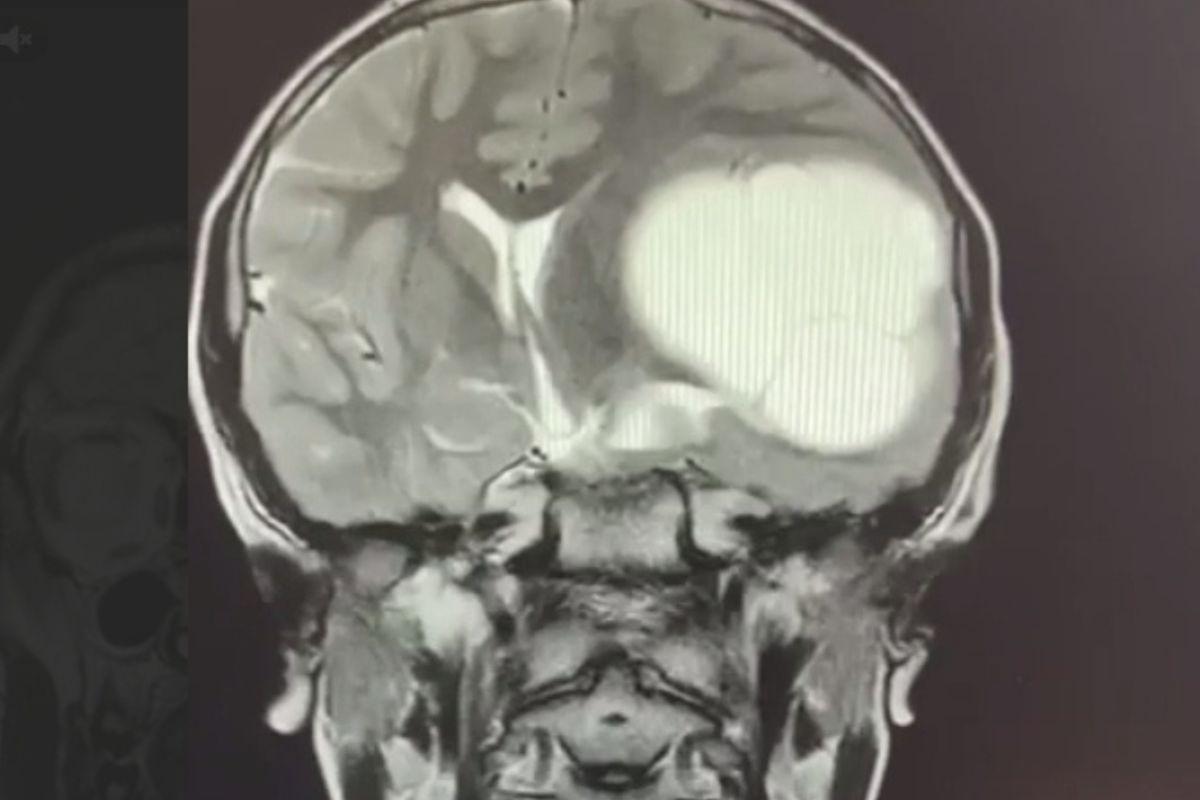

Сначала 12-летний Миша стал хуже учиться и жаловался на головную боль. Когда школьник стал неразборчиво писать и захромал, родители обратились в больницу. Там ребенку провели МРТ и диагностировали редкое заболевание – эхинококкоз головного мозга. Личинки червей проникают в мозг через кровоток, а заражение, как правило, происходит через грязные руки.

Мальчику провели сложную операцию в Челябинской детской областной клинической больнице и удалили образование в мозге. Сейчас ребенок восстанавливается, у него прошли головные боли и почти вернулась нормальная координация.